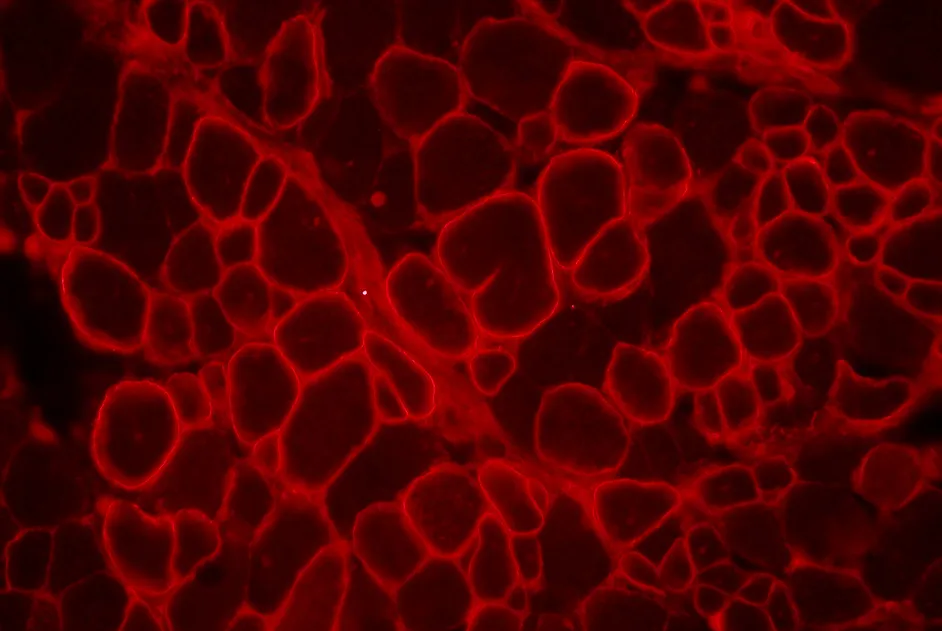

Maladie de Steinert : variants génétiques de MBNL1 et sévérité

Association des différentes formes génétiques du gène MBNL1 et de la sévérité de la maladie de Steinert.